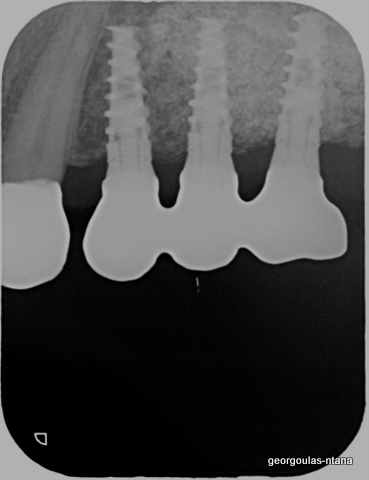

ΠΡΟΣΘΕΤΙΚΗ ΑΠΟΚΑΤΑΣΤΑΣΗ ΣΤΗΝ ΑΝΩ Κ ΚΑΤΩ ΓΝΑΘΟ ΚΑΙ ΤΟΠΟΘΕΤΗΣΗ ΕΜΦΥΤΕΥΜΑΤΩΝ ΜΕ ΚΛΕΙΣΤΗ ΑΝΥΨΩΣΗ ΙΓΜΟΡΕΙΟΥ

περισσότερα...